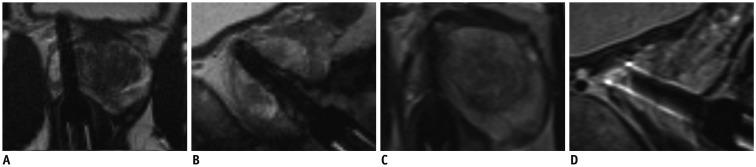

We retrospectively included patients with MRGB-2 after a negative MRGB-1 both between January 2006 and August 2016. This study included 62 patients (median age, 63 years; interquartile range [IQR], 58-66 years) with 75 sampled lesions during MRGB-2 left for analysis, and 63 lesions were resampled and 12 new lesions were sampled. Included patients had a prostate specific antigen (PSA) at MRGB-1 of 13 ng/mL (IQR, 5.8-20.0) and a PSA at MRGB-2 of 15 ng/mL (IQR, 9.0-22.5). All anonymized magnetic resonance imaging (MRI) data were retrospectively reassessed according to Prostate Imaging-Reporting and Data System version 2 by two radiologists. Images of MRGB were compared to determine whether the same prostate lesion was biopsied during MRGB-1 and MRGB-2. Descriptive statistics were utilized to determine the yield of clinically significant prostate cancer (csPCa) at MRGB-2. Gleason score of ≥ 3 + 4 was considered csPCa.

In 16/75 (21%) lesions csPCa was detected during MRGB-2. Of 63 resampled lesions, 13 (21%) harbored csPCa at MRGB-2. In two patients, csPCa was detected on repeat biopsy, while the volume of the lesion decreased between MRGB-1 and MRGB-2.

我们回顾性纳入了 2006 年 1 月至 2016 年 8 月间行 MRGB-2 检查的患者,这些患者的首次 MRGB-1 检查结果为阴性。本研究共纳入 62 例患者(中位年龄 63 岁;四分位距 [IQR],58-66 岁),MRGB-2 共分析 75 个活检部位,其中 63 个部位进行了重复活检,12 个新部位进行了活检。患者的 MRGB-1 前列腺特异性抗原(PSA)为 13ng/ml(IQR,5.8-20.0),MRGB-2 PSA 为 15ng/ml(IQR,9.0-22.5)。根据前列腺影像报告和数据系统(PI-RADS)第 2 版,由 2 名放射科医生对所有匿名化的磁共振成像(MRI)数据进行回顾性重新评估。比较 MRI 图像,以确定在 MRGB-1 和 MRGB-2 期间是否对同一前列腺病变进行了活检。利用描述性统计确定 MRGB-2 时临床显著前列腺癌(csPCa)的检出率。Gleason 评分≥3+4 被认为是 csPCa。

在 75 个病变中有 16 个(21%)在 MRGB-2 中发现了 csPCa。在 63 个重复活检的部位中,有 13 个(21%)在 MRGB-2 中发现了 csPCa。在 2 名患者中,在重复活检时发现了 csPCa,而在 MRGB-1 和 MRGB-2 之间,病变的体积减少了。